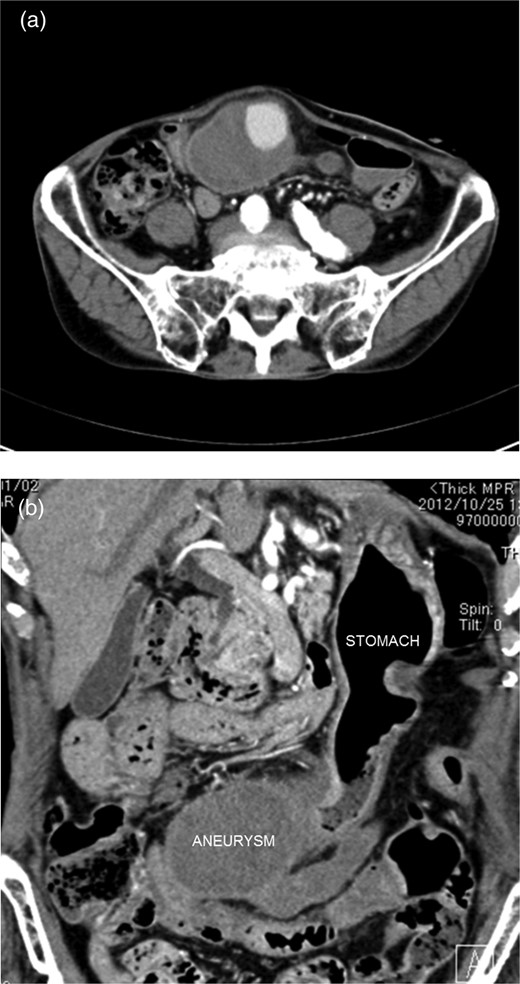

An 85-year-old man complaining of vague abdominal discomfort was admitted to our hospital. He had a medical history of arterial hypertension. Upon admission, his general status was stable. A pulsatile 8 × 7-cm mass in the right upper abdomen was noticed on clinical examination. Abdominal arterial aneurysm was diagnosed, and imaging studies were performed. Abdominal ultrasonography showed that the mass was present on the border of the greater curvature of the stomach, and blood flow was observed inside it (Fig. 1a and b). The mass was not connected to the abdominal artery. Computed tomography of the abdomen showed a huge arterial aneurysm in the right gastroepiploic artery, and the left gastroepiploic artery was meandering and expanding (Fig. 2a and b). There was no bleeding or ascites in abdominal cavity. Accordingly, an image diagnosis of GEAA was made. Because of the huge size of the aneurysm and the predicted high risk of perforation, surgical intervention was planned.

Computed tomography of the abdomen showed a huge arterial aneurysm in the right gastroepiploic artery.